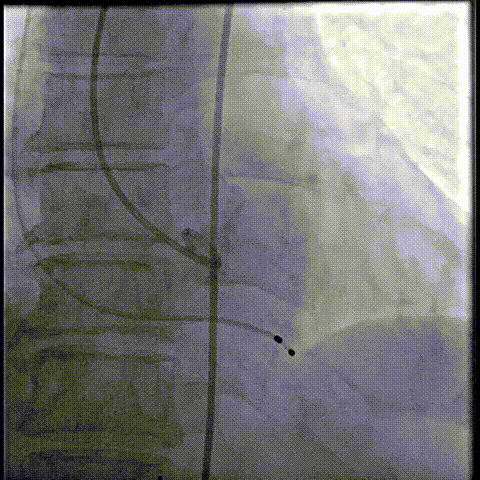

20球囊预扩

器械过弓柔顺

初始定位